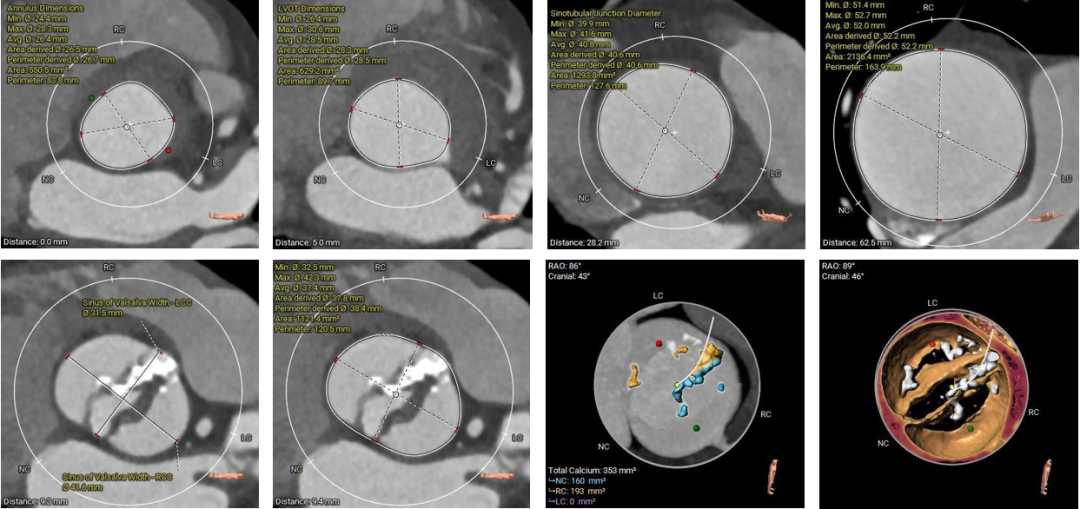

1.主动脉瓣瓣环周长83.8mm,平均周长径26.7mm。

2. Type0型二叶式主动脉瓣,左右冠不同窦,瓣叶中度钙化伴增厚,钙化分布不均匀,主要分布于瓣叶对合缘处。

3. 左右冠开口高度可,左冠瓣叶长度<瓣叶附着缘到冠脉开口处,右冠瓣叶长度>瓣叶附着缘到冠脉开口处,瓦氏窦、窦管交界内径尚可,升主动脉瘤样性扩张(最大直径52.2mm) 。

4. 流出道呈敞口型,心室腔偏大 。

1. Type0型二叶式主动脉瓣,瓣叶中度钙化伴增厚,钙化分布不均匀,LVOT呈敞口形,结合瓦氏窦、STJ,升主综合预估瓣膜锚定力难度适中,存在人工瓣膜形变、移位、瓣周漏风险。

2. 左右冠开口高度可,左冠瓣叶长度<瓣叶附着缘到冠脉开口处,右冠瓣叶长度>瓣叶附着缘到冠脉开口处,结合瓦氏窦、STJ内径及形态结构综合分析,预估冠脉堵塞风险偏低。

主动脉根部评估:

根部概览

冠脉情况

瓣上评估